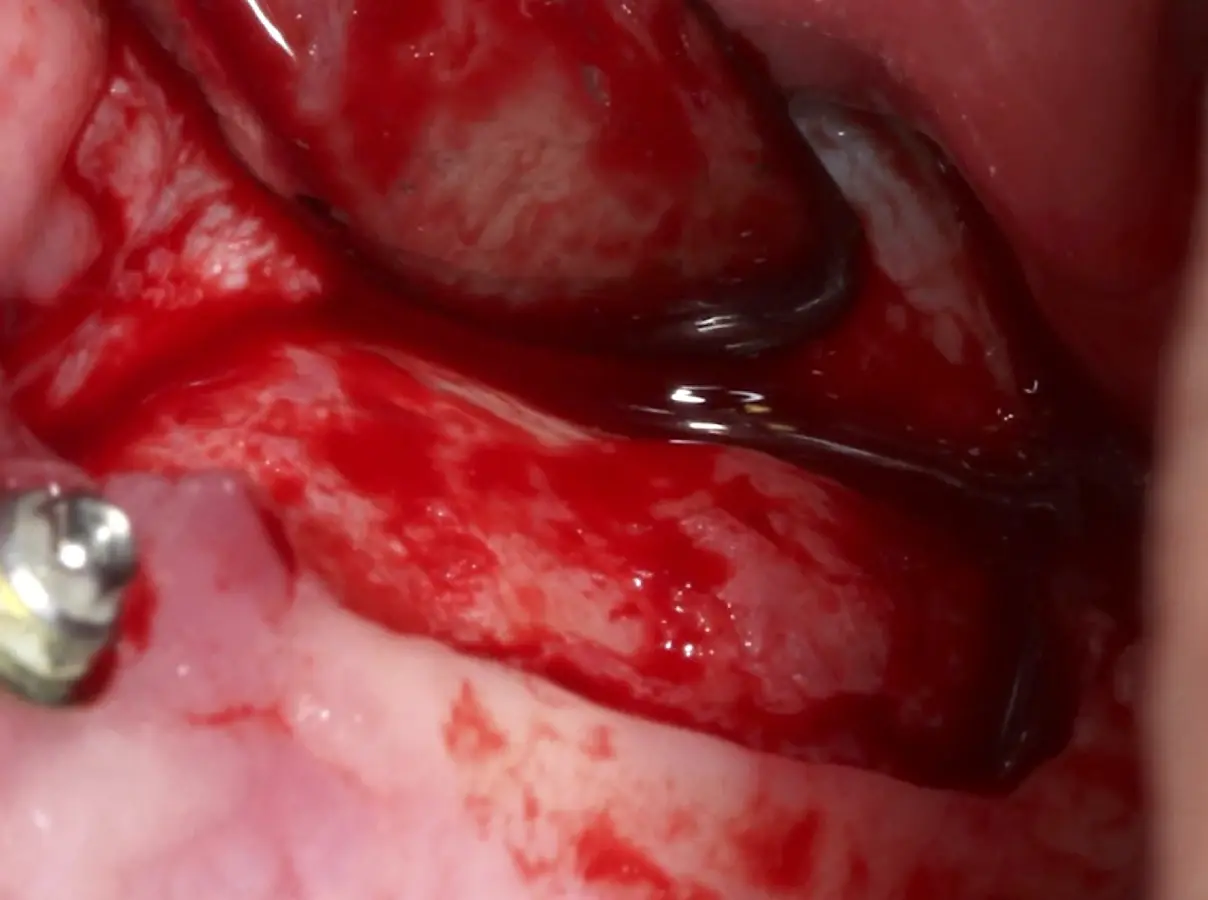

Se inicia la elevación de la membrana de Schneider con el inserto redondeado no cortante en forma de disco, empleando movimientos suaves. El levantamiento puede complementarse con elevadores convencionales, siguiendo la dirección mesiodistal. La fase de desprendimiento inicia con el piso y sigue hacia la pared mesial para terminar, y de ser necesario, hacia la pared posterior. Existen diversos insertos con angulaciones y longitudes para mayor accesibilidad16 (Figura 1).

El tipo de inserto a ser utilizado dependerá del espesor de la pared ósea. Si la pared es menor a 0.5 mm, es mejor utilizar insertos de desgaste para prevenir la ruptura de la membrana de Schneider; si el espesor es mayor a 0.5 mm, se puede utilizar insertos de corte de espesor medio (Figura 3).

El clínico puede retirar la tabla ósea o introducirla como “tienda de campaña” dentro del seno maxilar. En cualquiera de las alternativas, es importante evaluar la presencia de tabiques óseos y de la arteria postero alveolar superior.